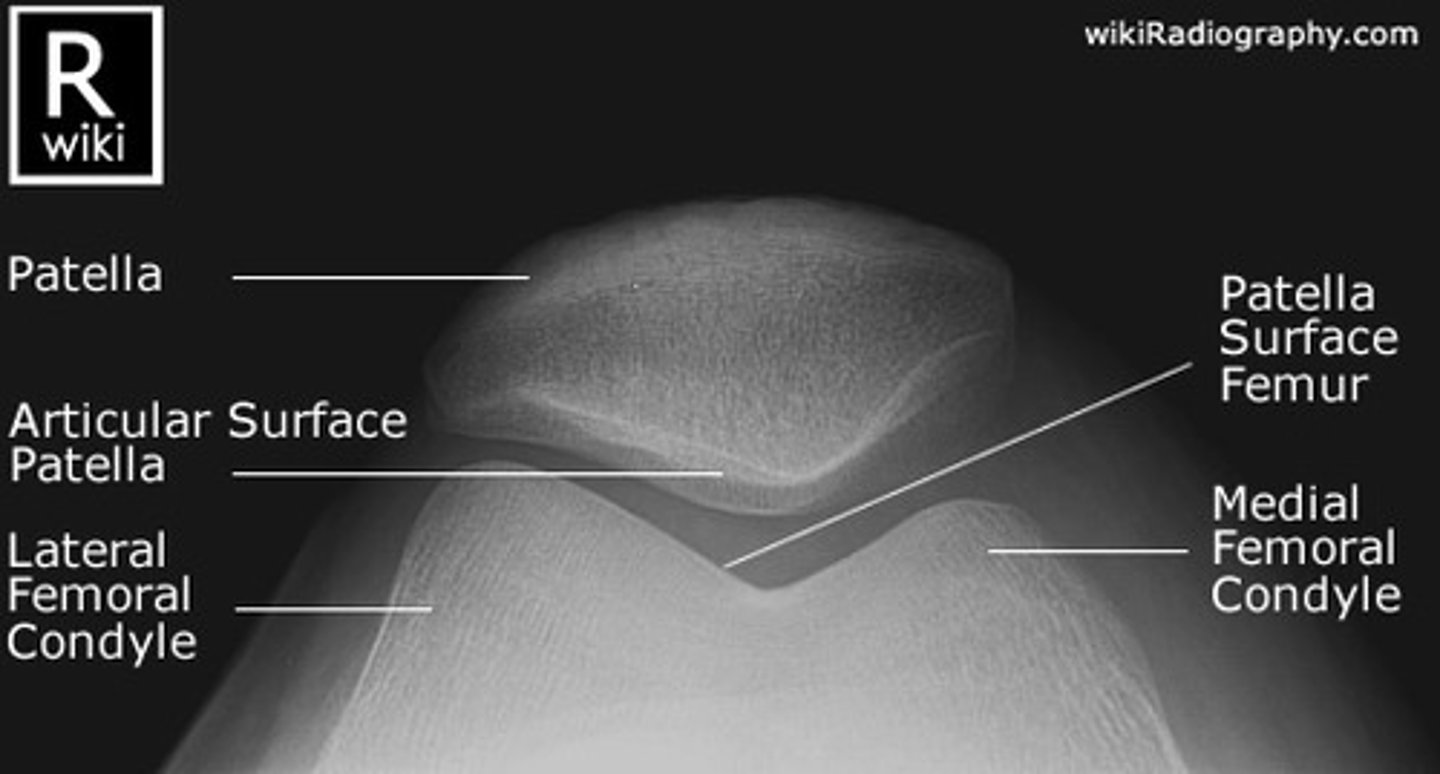

Describe, in the detail, how you would position the PATIENT for a SKYLINE projection of the knee (supero-inferior)

1. The patient sits on the x-ray couch with affected knee flexed over the edge.

2. If possible the knee should be flexed to 45 degrees.

3. Patient to lean back whilst keeping affected knee still to avoid primary beam.

4. The IR should be at the level of the inferior border of the tibial tuberosity

Describe, in the detail, how you would position the PATIENT for a SKYLINE projection of the knee (infero-superior prone)

▪ Patient lies prone.

▪ The IR can either be directly under the knee or in this case within the bucky (not using grid/AEC)

▪ Knee is flexed through 90 degrees.

How should you position the X-RAY TUBE for a infero-superior prone SKYLINE KNEE projection?

SID

Central ray

Centring point

SID: 115cm

Central ray: angled 15 degrees towards the knee (avoiding the toes)

Centring point: behind the patella